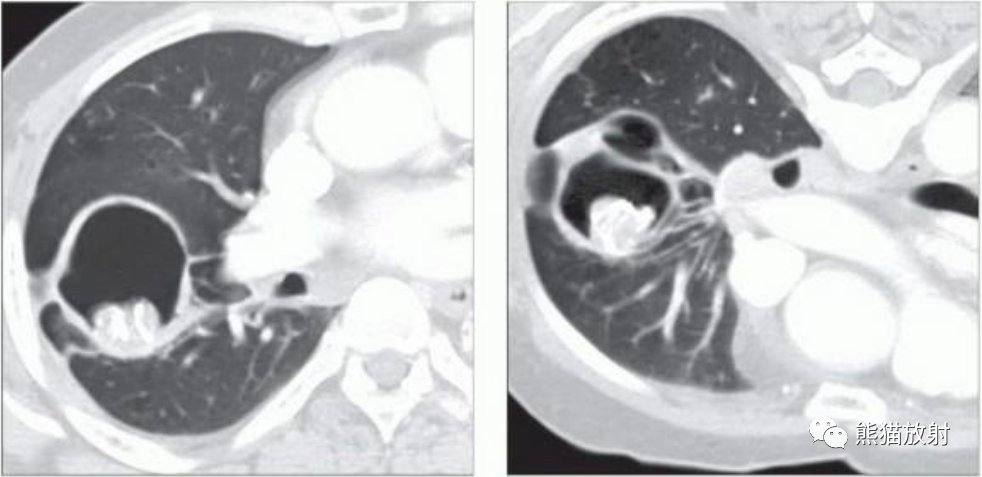

(左) 40岁男性,慢性右上叶肺结核病史,轴位CECT显示霉菌球,表现为腔内后部一部分钙化的结节。

(右)同一患者,俯卧CECT显示腔内霉菌球移动至重力依赖部位。在俯卧位重复低剂量 CT 有助于显示疑似霉菌球的腔内活动性。